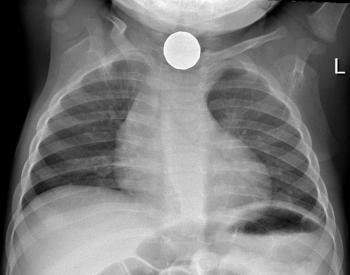

Cómo actuar cuando un niño ingiere accidentalmente un cuerpo extraño

Radiografía cuerpo extraño

Hasta el 20% de cuerpos extraños quedan alojados en esófago y con más frecuencia en su tercio medio. Los síntomas que refieren los pacientes son dolor en la zona central del pecho, dolor con la ingesta, sialorrea (acumulación y salida de saliva por la boca por la imposibilidad de tragar), vómitos y rechazo a la ingesta. Pueden producir complicaciones como perforación del esófago o neumonías por aspiración. Es recomendable, independientemente del tipo de objeto ingerido, su extracción mediante endoscopia.

Objeto en esófago